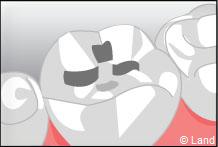

Les traitements possibles pour les stades de la carie où seuls l’émail et la dentine sont touchés peuvent se faire avec de l’amalgame qui est un matériau indiqué dans la restauration des petites et moyennes cavités.

L’amalgame est utilisé sous forme de capsules prédosées et avant son utilisation est préparé par un vibreur qui mélange les composants de façon homogène. Il se présente sous la forme d’une pâte, plastique qui durcit dans la cavité nettoyée de la lésion carieuse et devient pratiquement aussi résistant que les tissus dentaires.